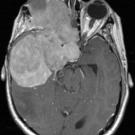

Genome Sequencing Uncovers Therapy for Rare Brain Tumor

Brain tumors are among the deadliest forms of cancer, due in large part to their sensitive location and the challenge of performing surgery to remove them. New research led by David Solomon,MD, PhD, an assistant professor in the Department of Pathology at UC San Francisco, provides much-needed